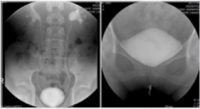

좌측 그림은 방광요관역류 (우측 grade II, 좌측 grade IV)가 있는 4세여아의 배설성방광요도조영술 (voiding cystourethrography) 사진이고 우측 그림은 자궁절제술 을 시행하고 지속적인 질누출을 호소하는 환자에서 보이는 방광질루 (vesicovaginal fistula) 소견이다. 우측 그림에서 환자의 방광은 배뇨를 시작하지 않은 상태 (funneling 및 bladder neck opening 이 되지 않은 상태)에서 질로 요누출이 관찰되고 있다.